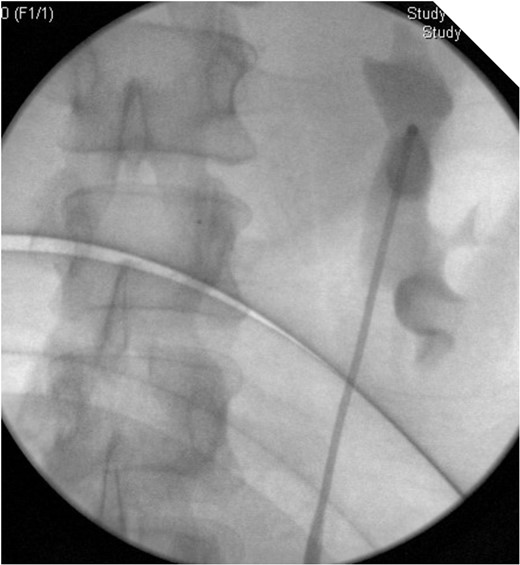

On table Pyelogram confirmed intact left collecting system and ureter.